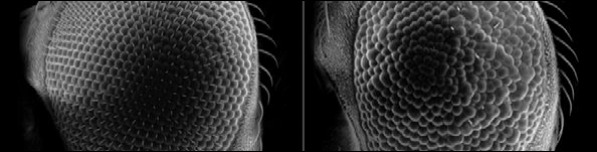

And while you can dissect a fruit fly to learn what's gone on; it isn't an easy job. Fortunately in this case you can gauge the extent of the interaction of the two human proteins by the amount of disorder caused in the eyes of the flies. You can see just this in this picture, normal fly on the left and disordered eye on the right.

Of course the physicist in me sees a simple experiment where you just get a load of flies to breed and then bung 'em in the scanning electron microscope for their eyeball close-ups. In fact my lack of experience with biological systems means I had completely forgotten that a major part of the research is breeding up a large population of flies with all the right genes in all the right places to work with in the first place.